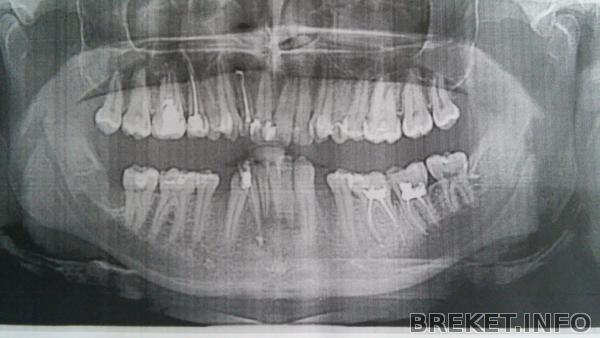

Панорама после удаления 8-ки и перелечивания каналов депульпированных зубов: